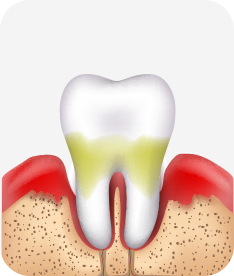

치주염 단계별 증상

건강한 상태

치아 주위의 잇몸이 핑크색을 띄며, 잇몸에서 피가 나지 않음.

스케일링을 6개월 ~ 1년 주기로 받고 올바른 칫솔질로 건강한 치주 조직을 유지

치은염 (초기~중기)

치아 주위의 잇몸이 붉게 부어 있으며, 칫솔질 등을 할 때 피가 남.

스케일링 주기의 조절이 필요할 수 있으며, 올바른 칫솔질을 시행하여야 함.